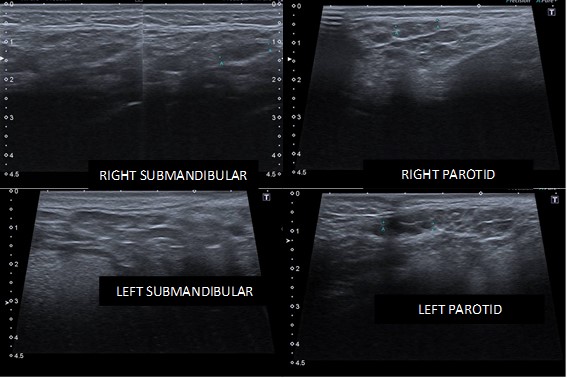

One month after the last consultation, the patient returned with an imaging examination (US with a 12.0 MHz linear transducer) of the parotid and submandibular glands. Images suggestive of parotid glands with preserved dimensions, with heterogeneous diffuse echotexture, characterized by solid-cystic (predominantly solid) and hypoechoic areas affecting the entire parenchyma, measuring up to 1.3cm, with preserved flow on Doppler were evident. The submandibular glands were reduced in size with a diffusely heterogeneous echotexture, characterized by solid-cystic (predominantly solid) and hypoechoic areas affecting the entire parenchyma, measuring up to 1.3cm, with preserved Doppler flow.

There was the presence of numerous small bilateral diffuse cervical lymph nodes, especially on the left, with a determined appearance, as shown in figure 3.

Figure 3: Ultrasonography with a 12.0 MHz linear transducer, of the parotid and submandibular glands, bilaterally.